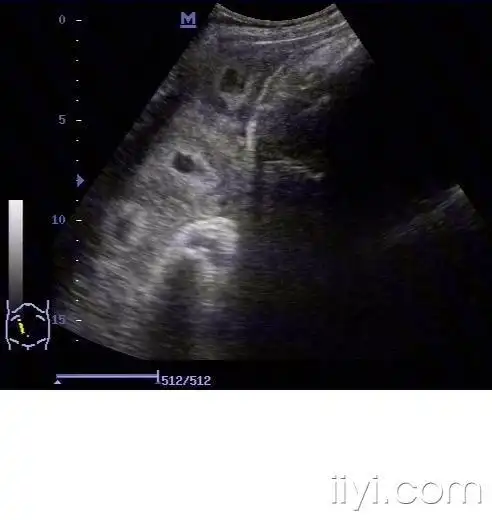

【分享】少见的胎盘血窦!